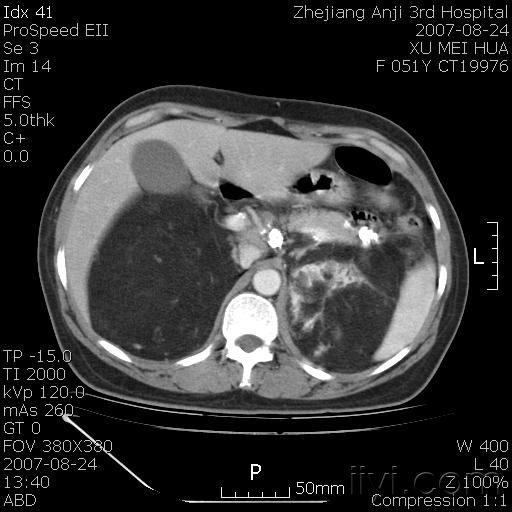

以下是引用还珠格格在2007-8-27 10:19:00的发言:[br]双侧肾脏形态失常,可见巨大的以低密度脂肪为主的混合性肿块,占据中下腹,残留的肾组织轻度强化,增强后肿块内实质部分呈峰窝状强化,低密度区无强化。另左侧肾盂轻度积水。根据病史 考虑 双肾血管平滑肌脂肪瘤可能性大。[br] 鉴别诊断 1、脂肪瘤,境界清楚,肿块内完全是脂肪,几乎没有软组织成分; 2、畸胎瘤:罕见,除有软组织成分外,另一特征是有钙化或骨化影组织。